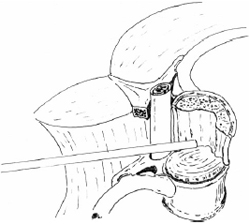

A costotransversectomy was performed and tumour encountered at the posterior aspect of the pedicle. Tumour removal was carried out until the pedicle was removed and a clear corridor available for introduction of the endoscope via a lateral approach (Fig. 3). Tumour removal under endoscope assisted control was accomplished with the aid of curettes and bipolar diathermy until a compete macroscopic clearance achieved. A Pyramesh titanium cage (Soframor-Danek) was packed with bone graft and impacted into the defect between T10±T12 for anterior column stabilization (Fig. 4). Methylmethacrylate was also inserted into the dead space arround the cage. Fixed angle pedicle screws (HorizonTM Soframor-Danek) were inserted into T10 and T12 with rods

Fig. 3 Approach angle of endoscope to view tumour without cord manipulation.